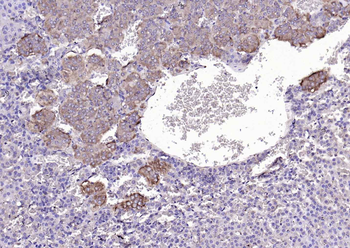

RARB Rabbit Polyclonal Antibody [orb11327]

FC, ICC, IF, IHC-Fr, IHC-P, WB

Bovine, Canine, Gallus, Porcine, Rat

Human, Mouse

Rabbit

Polyclonal

Unconjugated

50 μl, 100 μl, 200 μlTIG2 Rabbit Polyclonal Antibody [orb11481]